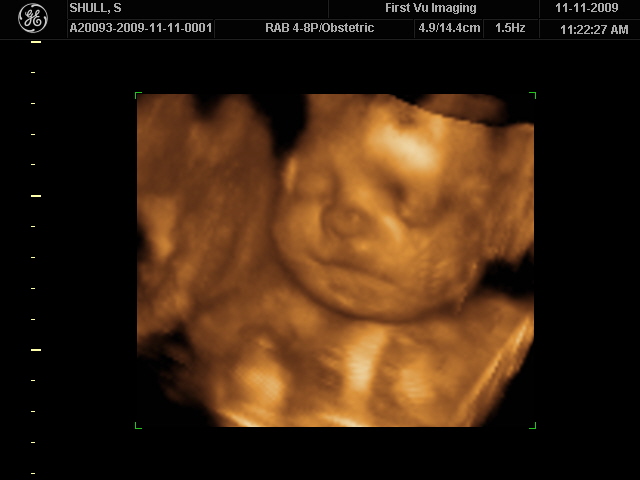

It was June 7, 2009 and I had a 8 month old daughter and was getting braces on that morning. I know…braces. I had been dealing with some health issues for years and years and finally found a team of doctors who knew how to fix the problem. I would be needing braces, my tonsils removed and myofuncional therapy. I was dreading all of it. Our local photographer came over and took a few pics of us to celebrate our 8 month old and so that I could have a few family pictures before the dreaded braces…